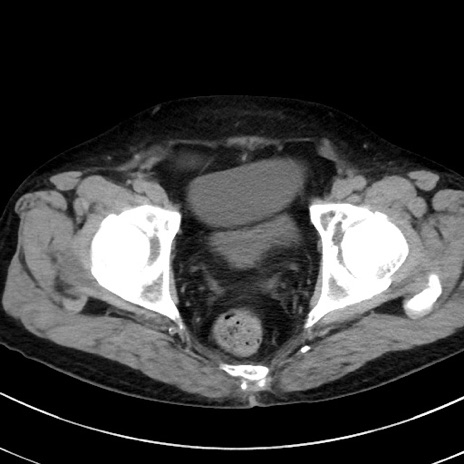

症例38(横断像)

【症例】70歳代 男性

【主訴】腹痛・嘔吐

【現病歴】昨晩より、嘔吐・腹痛あり。今朝になっても嘔吐あり。来院。

【既往歴】心臓バイパス手術、開腹胆摘、腸閉塞

【身体所見】BP 107/71mmHg、HR 116/min、腹部:平坦、軟、下腹部に軽度圧痛あり。反跳痛なし。

【データ】WBC 15100、CRP 0.32